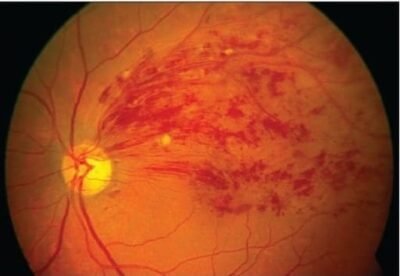

4. Retinal Vein Occlusion

The retina has numerous blood vessels for its nutrition and at times one of the main vessel or its branch can get blocked due to various reasons. Retinal vein occlusion is usually related to conditions that affect blood vessels.

There are many risk factors and the common ones include,

- High blood pressure

- Diabetes

- High cholesterol

- Smoking

- Age above 50 years

If you have blurring or foggy vision and have one or more of the risk factors, it is important to consult your Ophhalmologist for a dilated eye examination to confirm the diagnosis. At times further tests are done including OCT ( Optical Coherence Tomography) to measure the retinal swelling or FFA ( Fundus fluorescein Angiography) to check the blood flow and identify areas of leaking vessels or any blockage.

Treatment options include eye injections or laser treatment. In general the visual outcome depends upon the severity and the time of onset of treatment.